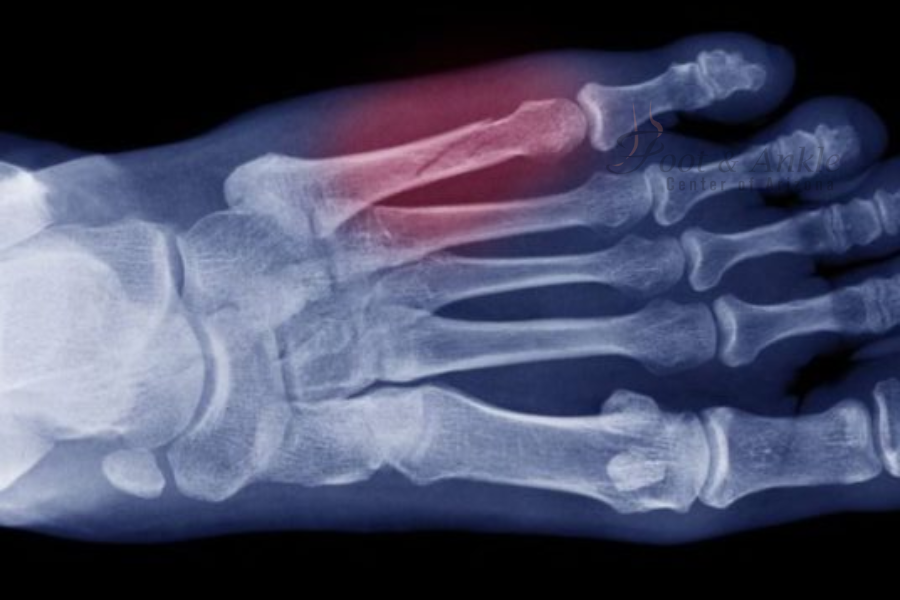

The metatarsals are long bones that link the ankle to the toes. The breaking of any one of these bones is called a metatarsal fracture. There are various causes of such types of fractures, including trauma, overuse, and stress. One of the most common bones fractured of the foot is the second metatarsal.

Diagnosis of Metatarsal Fracture

In the event of suspicion of metatarsal fracture, seek help from a doctor immediately. A health professional will, most of the time, perform an examination and request imaging studies such as X-rays to confirm the presence of the fracture.